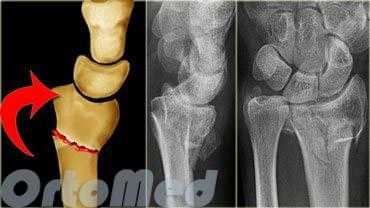

Представляет интерес способ остеосинтеза головки лучевой кости, предложенный группой швейцарских ученых АО [2]. В своей работе авторы предлагают классическим дорсолатеральным доступом обнажать место перелома и осуществлять репозицию костных отломков специальными узкими щипцами, использующимися в хирургии кисти, или тонкими спицами Киршнера. При наличии вдавленных областей предлагается их репонировать, а возникшие дефекты заполнять губчатой костью из расположенного рядом надмыщелка. Стабилизация достигается шурупами 1,5 мм или 2,0 мм, которые вводят в различных плоскостях и на разных уровнях с погружением их головок в хрящ суставной поверхности (рис. 1).

За период с 2010 по 2012 гг. в 1-ом травматологическом отделении городской клинической больницы No71 города Москвы выполнено 5 эндопротезирований головки лучевой кости. Все больные поступили в стационар по ургентным показаниям и имели оскольчатые переломы головки лучевой кости III типа по Mason, которые не подлежали реконструкции, что составляет 19% всех повреждений головки лучевой кости (рис. 1) [9].